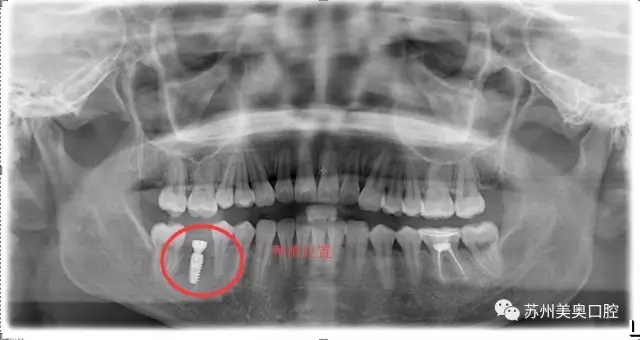

光学显微镜主要用于放大微小物体成为人的肉眼所能看到的仪器,所以被广泛应用于医学研究和临床手术中。口腔显微种植高精度可以精确到1毫米,将细微的口腔解剖结构放大近30倍,患者看到的下图仅仅放大了10倍。

相比于传统肉眼观察,显微口腔治疗为医生提供了聚焦光源和放大的清晰视野,明确分辨微小的神经血管,便于医生更换更小更精密的工具,进行的治疗,让种植牙更加安全高精。苏州美奥显微口腔治疗利用现代医疗科技一步一步实现着口腔治疗微观高精化。

我很久之前就想把牙齿种起来,只是担心牙槽骨那里已经很狭窄了,再加进一颗钉子会不会很不安全。直到看到美奥口腔的显微种植,术区可以放大到30倍,口腔视野很清晰,觉得种植很安全,所以才决定进行显微种植牙治疗。”